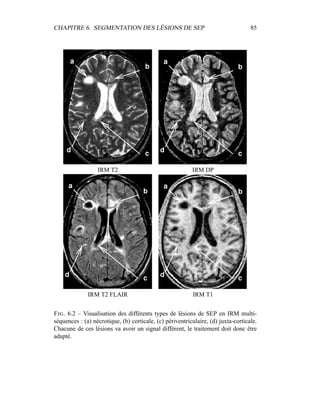

K

k=1

πkp X|(Z = k, Θ)

CHAPITRE 4. SEGMENTATION EN TISSUS 47

Les {πk} sont les proportions de chaque classe : K

k=1 πk = 1. Ces paramètres

sont inconnus et K, le nombre de composants, est un hyperparamètre à ajuster.

Dans le cas particulier des mixtures de gaussiennes, p X|(Z = k, Θ) est une

combinaison de K gaussiennes de paramètres {µk, Σk} :

p X = x|(Z = k, Θ) = Gµk,Σk

(x)

=

1

(2π)d/2|Σk|1/2

e− 1

2

(x−µk)T Σ−1

k (x−µk)

d est ici la dimension des données X. Avec un tel modèle, les paramètres sont :

Θ = {π1, . . . , πK−1, µ1, . . . , µK, Σ1, . . . , ΣK}

L’algorithme EM fournit ainsi une solution très élégante à l’estimation des pa-

ramètres Θ en fonction des données x. En effet, dans le cas d’un modèle de mix-